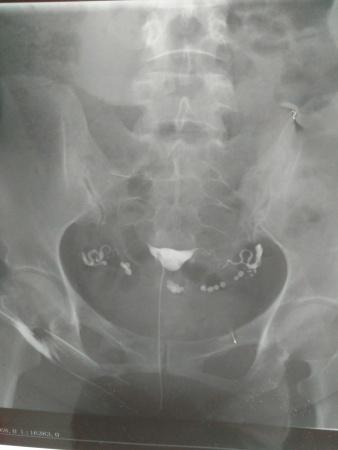

输卵管碘油造影的片子,请帮忙看看,医生意见不一致。

[attach]2075109[/attach]

一位认为输卵管通,但弥散不良,另一位认为通而且弥散也正常。请大家赐教。

很通畅的,图片也很清晰。

通的,两侧都有造影。